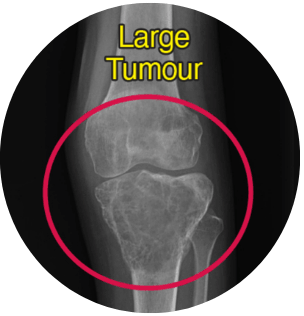

A 26 years old patient came to MIOT International with severe pain in the left knee and an inability to walk. What initially appeared as a musculoskeletal issue was soon diagnosed as something far more serious – a large, rare tumour involving the upper part of the leg bone near the knee. The location of the tumour made this a high-risk and limb-threatening condition. Conventional treatment would likely have resulted in permanent loss of knee movement, or even loss of the leg.

Imaging and diagnostic tests revealed a large tumour affecting the upper tibia (leg bone near the knee). The growth was aggressive and located very close to major blood vessels and nerves. This placed the patient at high risk of limb loss and potential malignant transformation.

The tumour’s location made surgery extremely complex:

Close proximity to major arteries, veins, and nerves

Before

After